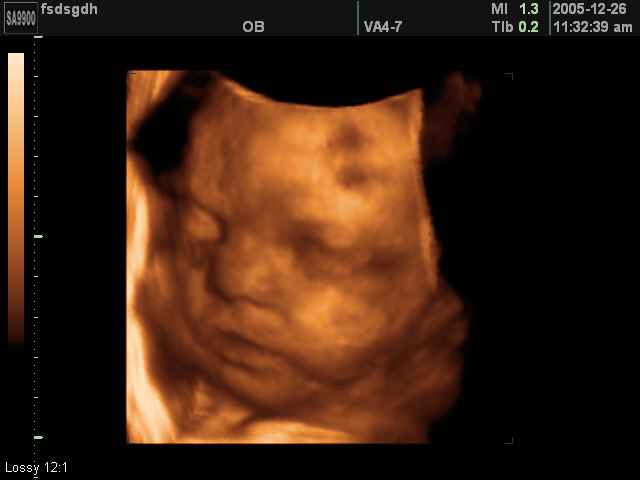

3D Fetal Face Ultrasound Scan Photos | Dr N Layyous

3D Fetal Face Ultrasound Scan Photos